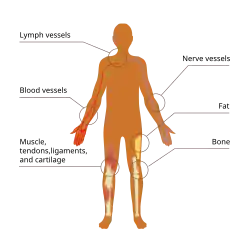

A sarcoma is a rare type of cancer that arises from cells of mesenchymal origin.[1][2] Originating from mesenchymal cells means that sarcomas are cancers of connective tissues such as bone, cartilage, muscle, fat, or vascular tissues.[2][3]